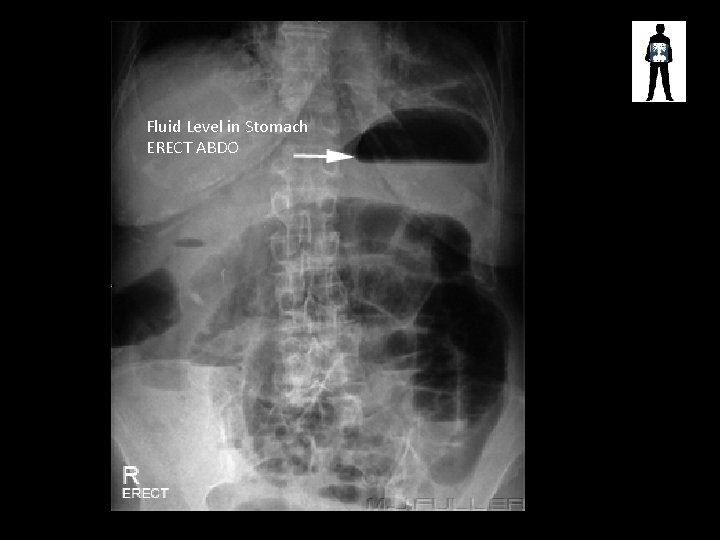

Fluid Level in Stomach ERECT ABDO

Normal Large Bowel Pattern Faecal Matter